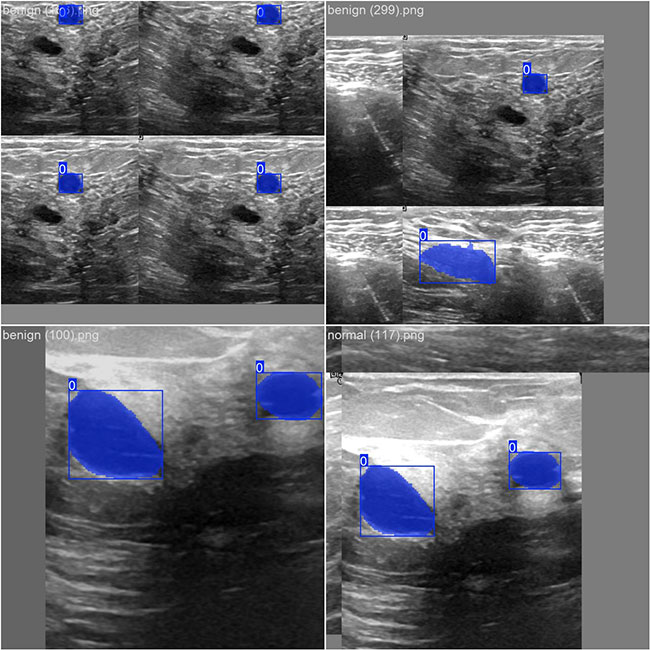

部分数据集图像如下图所示:

部分标注如下图所示:

这种数据分布方式保证了数据在模型训练、验证阶段的均衡性,为 YOLOv8n 模型的开发与性能评估奠定了坚实基础。